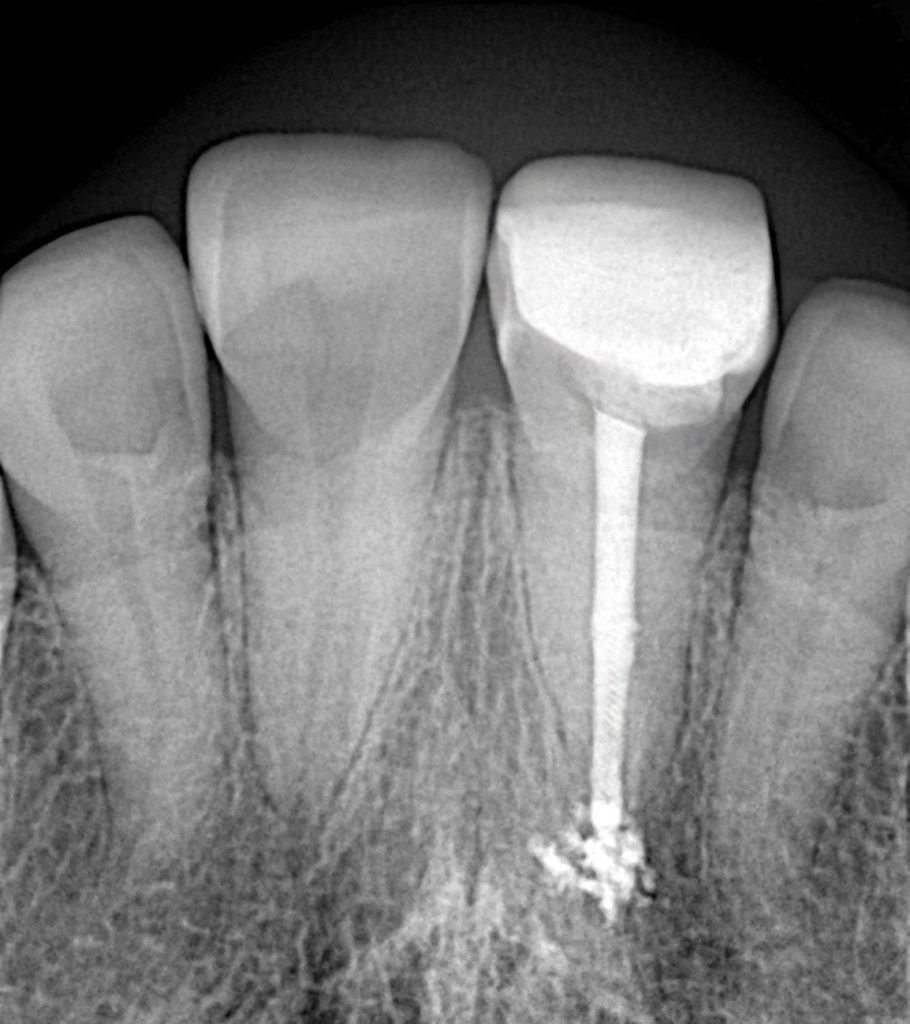

1 Pre-operative Assessment

Clinical exam revealed a coronal fracture exposing previous access and visible sealer remnant. Periapical radiograph confirmed a metallic fragment lodged in the apical third with a faint radiolucency (Fig 1–2).